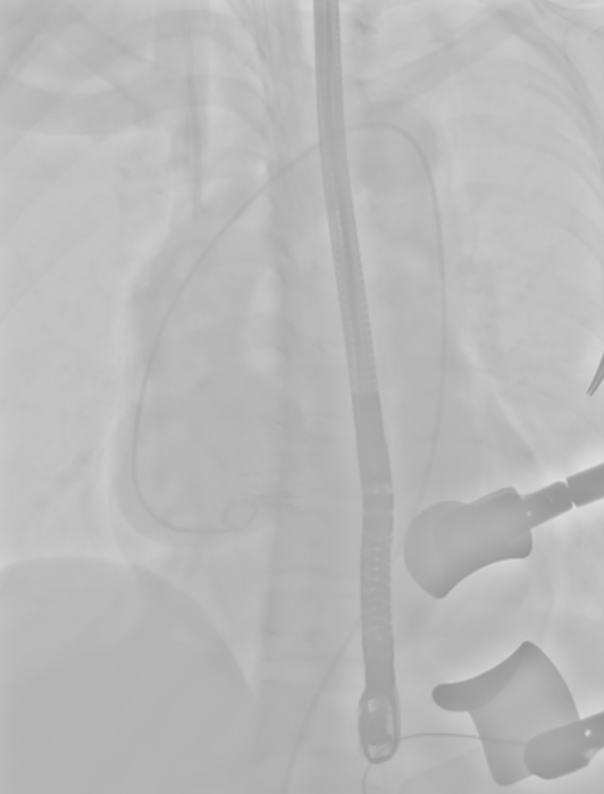

手术当日,在周亚峰教授指导下,心内、胸外等多学科团队充分发挥协作优势。术中凭借经食道超声实时导航,精准定位心尖穿刺点并预缝双层荷包。然后,通过DSA透视引导,将人工瓣膜经心尖输送系统沿导丝轨道推送至病变主动脉瓣区。

团队娴熟操作导丝输送系统,精准调整角度,确保J-Valve人工瓣膜的定位翼准确嵌入主动脉窦部。瓣膜释放后造影显示,人工瓣膜形态位置理想,原有的重度主动脉瓣反流消失。整个关键瓣膜置换步骤仅耗时30分钟,并且患者术后即刻苏醒,未出现传导阻滞、出血等并发症,复查超声证实人工瓣膜功能良好。目前患者已平稳出院,恢复良好。